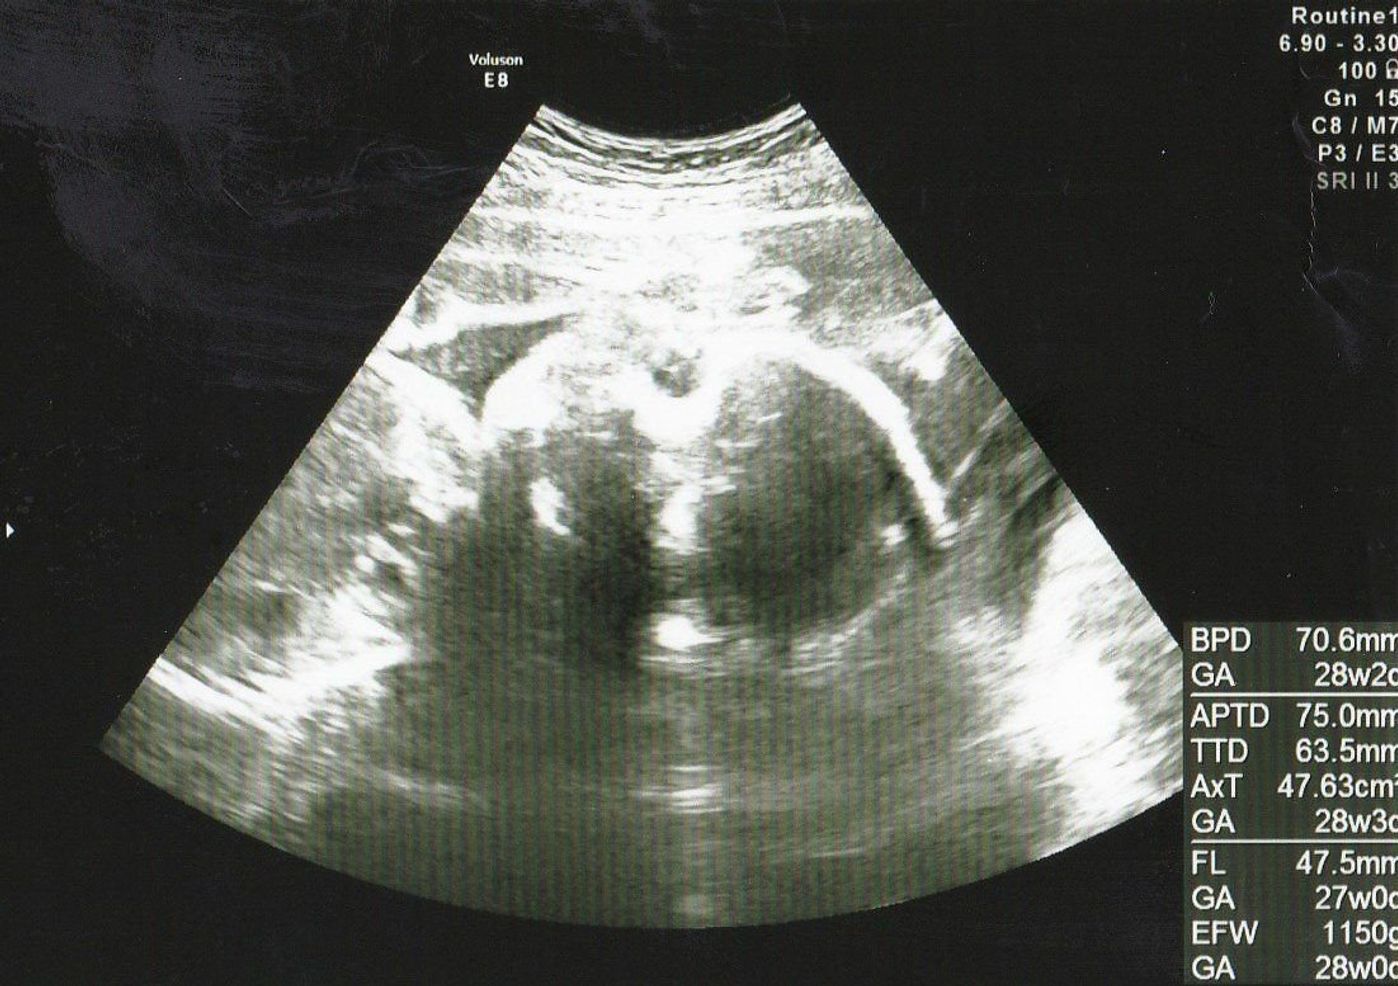

エコーでは全身が入っていますが、 子宮壁?やへその緒などに隠れて、 顔は全く見えませんでした。 手足がちょこんとついて、 お座りしているような様子は可愛いですが、 顔立ちが分からないので、少し物足りないですね。 23週0日 こちらは23週の時の キュアエコー 今回は、プリキュアオールスターズNewStageに登場する、キュアエコーの図案を紹介したいと思います。 まずは作った作品がこちら。 『キュアエコー』をアイロンビーズで作ってみた キュアエコー可愛いですね。 Theマジカル戦士!という感じの外見をしていると思います。 色・サイズ:OMBRE / 43 (265~27cm) サイズ感:期待していた通り このシリーズの紐タイプのサイズ42を使用していました。 サイズ感がピッタリ過ぎて、ワンサイズ上の43を今回頼んでみました。 やや余裕があり、期待通りのものでした。 色違いでeccoを